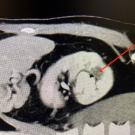

A 61-year-old man with obesity, no significant medical or surgical history, and a 40 pack/year smoking history presented to the clinic with urinary urgency and frequency.